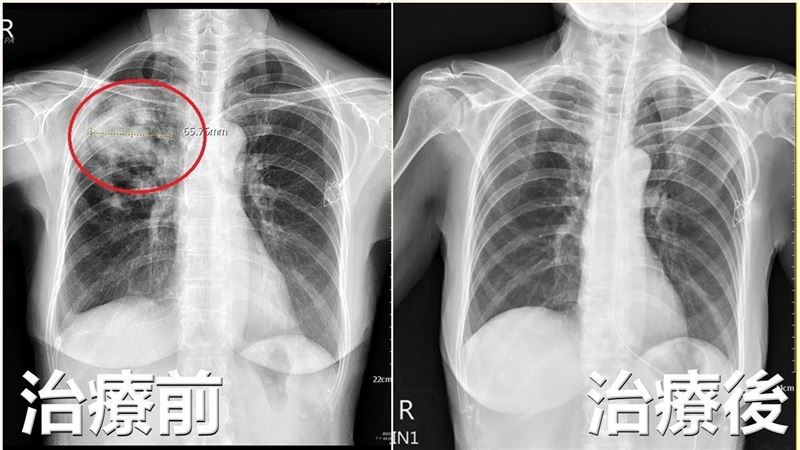

▲台中市一名65歲王姓婦人肺部被細菌感染出現「破洞」,醫師抽血檢查確認是隱球菌感染引發的肺炎,投藥半年才康復。(圖/亞大醫院提供)

根據患者照肺部X光後,發現右上肺葉單側有感染現象,像被啃破「一個洞」,由於患者因化療後免疫力大幅下降,醫師決定抽血檢驗「隱球菌」抗原試驗,抽血報告果然為陽性反應,確認為「隱球菌肺炎」,投以抗生素治療,並配合化療進度,大約半年時間,患者才順利完成治療。